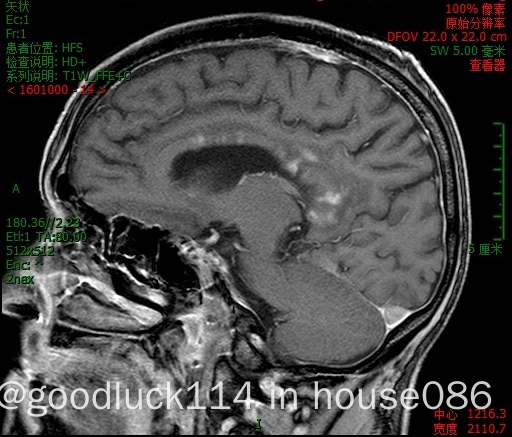

高龄取不了病理,医院做不了pet-ct,做了头颅ct和mri,发现颅内占位性病变,怀疑原发或转移,但胸部ct腹部ct和肿瘤标志物都没有明显异常,也没有除神经系统外其他系统的症状,mri增强结果不像是胶质瘤,高度怀疑是原发性中枢淋巴瘤。

这个年龄熬不过化疗,医生给的方案是单药服用奥布替尼,或者全脑放疗,或者联合。

有看到说全脑放疗的损伤很大的,不知道究竟怎么样。单用奥布替尼的损伤呢?

爷爷上周还能在关心时事看海峡两岸,这周已经不知道自己在哪里,分不清白天黑夜了。